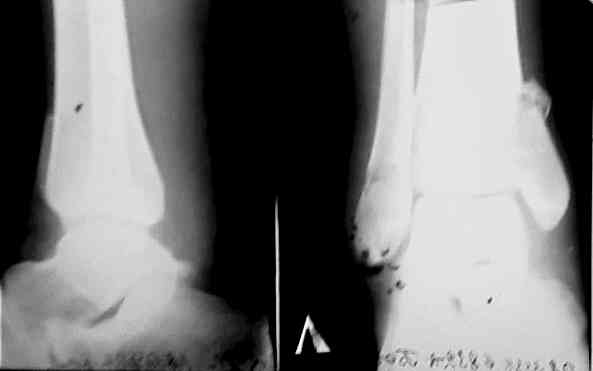

Доброго времени суток,коллеги! Вчера обратился на консультацию 22-летний больной. Травма 26.09.06. 30.09.06 оперирован. 30.11.06 Гипс снят снимки после снятия гипса представляю.

У меня возникает вопрос: Что делать? оставить как есть (нюх подсказывает, что нет) или переделать? (но открывать в 2 месяца ?) Отека нет,движения ограничены , нагрузки небыло 2 месяца. Помогите советом,pls

На мой взгляд учитывая возраст больного оставлять так нельзя. на данных рентгенораммах четко видно что таран находится в подвывихе, допустим больной начнет разработку, его устроит объем движений, в дальнейшем неизбежно разовьется дефартроз и больной будет страдать от болей. Я бы рекомендовал реконструкцию. Все хорошо продумать, это вмешательство не подарок, и произвести корегируюшую отстеотомию, не принебригая в послеоперационном периоде антиостеопоротической терапией. Удачи с ув. Куликов.

Как говорил мой шеф - снимки корзиночные (в смысле в корзину) - трудно советовать что либо. Сделайте свеже-хорошие пли-и-з. А пока пусть восстанавливает локомоцию в суставе - это не во вред.